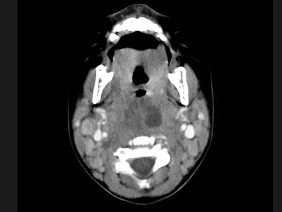

[多选题] 10个月大的婴儿,发热,曾患中耳炎,CT扫描如图所示,请选择正确的描述或诊断()A . 咽后壁软组织肿胀B . 其内密度不均C . 颈椎骨质未见明显异常D . 考虑为咽后壁脓肿E . 考虑为咽后壁寒性脓肿

[多选题] 10个月大的婴儿,发热,曾患中耳炎,CT扫描如图所示,请选择正确的描述或诊断()A .咽后壁软组织肿胀B .其内密度不均C .颈椎骨质未见明显异常D .考虑为咽后壁脓肿E .考虑为咽后壁寒性脓肿